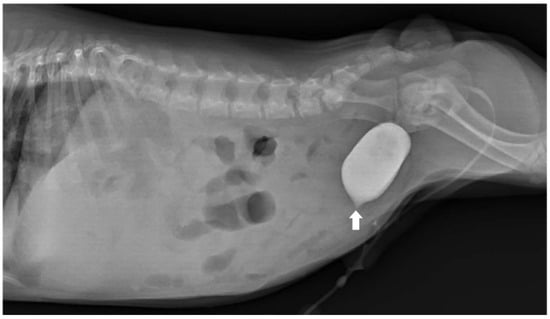

Concurrent Congenital Umbilicobiliary Fistula and Vesicourachal Diverticula in a Dog

Congenital umbilicobiliary fistula is a rare disease reported in humans and dogs. A 2-month-old, intact, male French Bulldog presented with a greenish-yellow discharge dripping from the umbilicus since birth. Complete blood count and serum biochemistry were within normal limits, but serum alkaline phosphatase [...] Read more.

Congenital umbilicobiliary fistula is a rare disease reported in humans and dogs. A 2-month-old, intact, male French Bulldog presented with a greenish-yellow discharge dripping from the umbilicus since birth. Complete blood count and serum biochemistry were within normal limits, but serum alkaline phosphatase activity was mildly elevated. A positive contrast cystogram was performed to rule out a patent urachus and confirmed the presence of a vesicourachal diverticula, a type of urachal anomalies. An abdominal ultrasound and computed tomography fistulogram demonstrated a communication between the umbilicus and common bile duct, which suggested an umbilicobiliary fistula. Surgical correction of the umbilicobiliary fistula and vesicourachal diverticula was successfully performed with an uneventful recovery. Histological analysis of the fistulous tract demonstrated a cuboidal/columnar lining epithelium that transitioned to squamous epithelium near the umbilicus. Agenesis of the gallbladder was noted. The application of multiple imaging techniques in the diagnosis and surgical correction of these congenital abnormalities (umbilicobiliary fistula, gallbladder agenesis, and vesicourachal diverticula) was beneficial for treatment planning and outcome. Full article